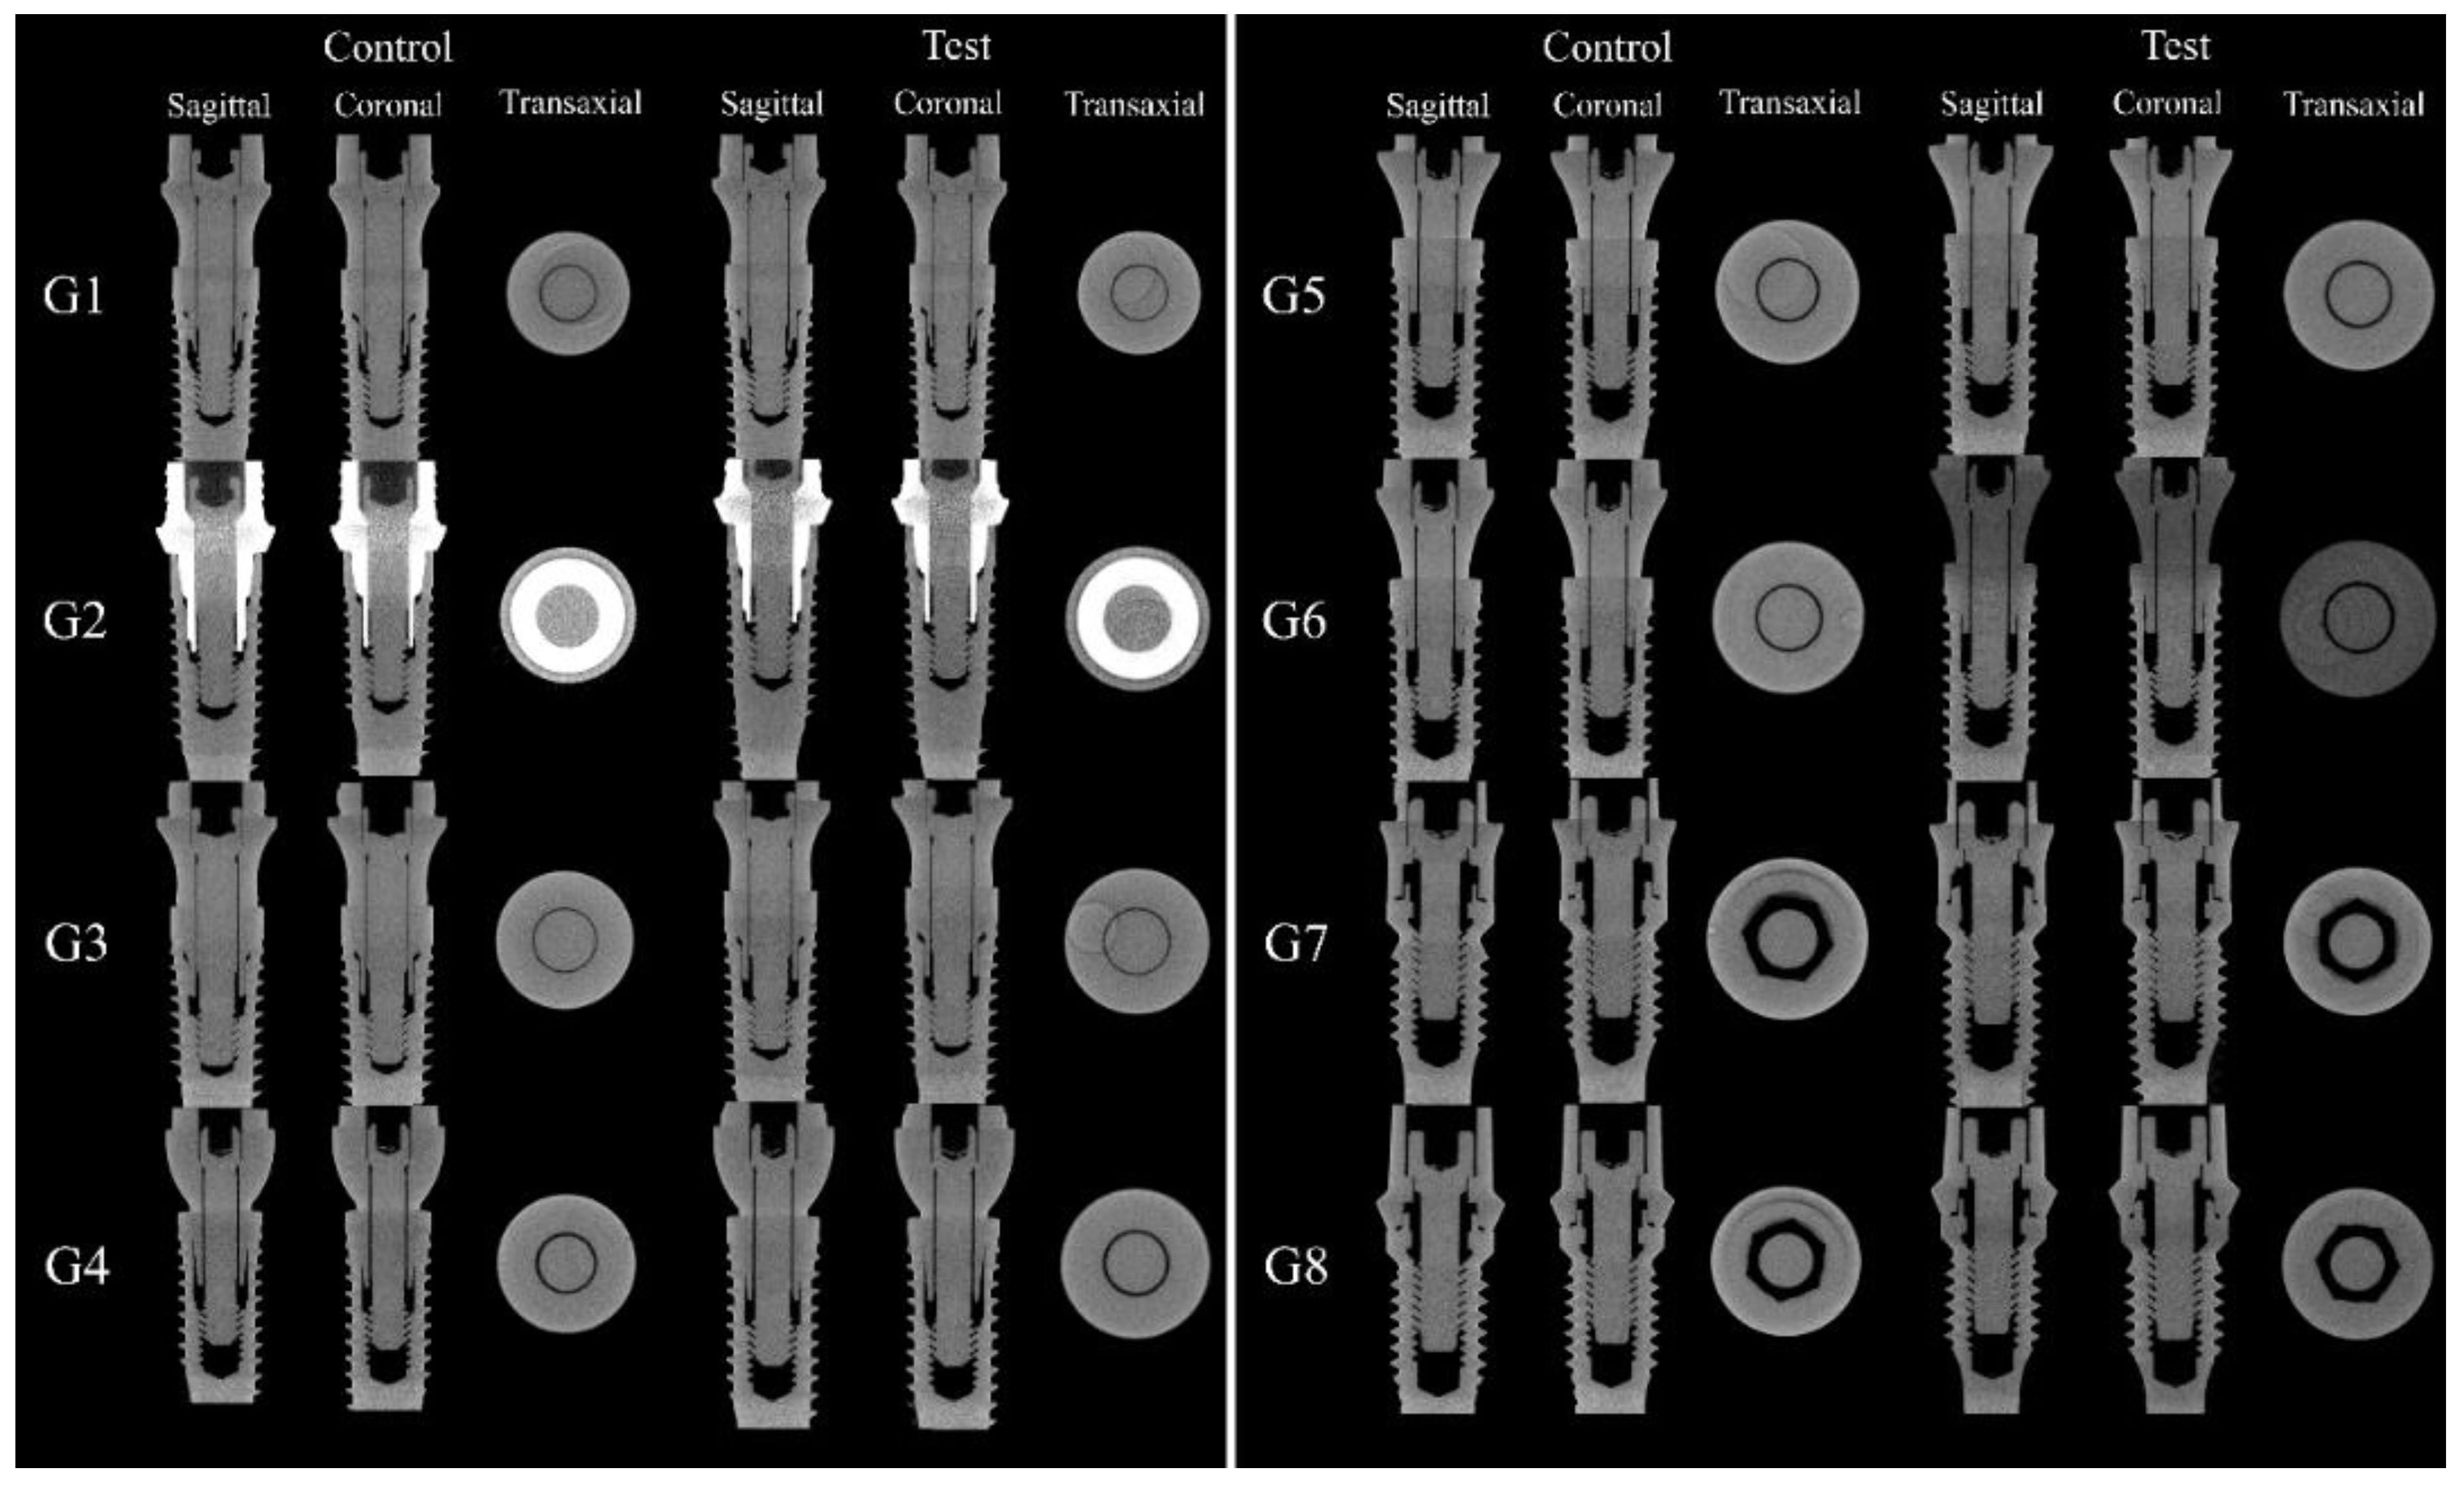

MicroCT and SEM analyzes showed that no microgaps were seen in the IAI region and in the contact region between the screw head and the abutment, as can be seen in Figure 8 and Figure 9.

The MicroCT and SEM analysis demonstrated the existence of adaptation of the abutments to the prosthetic platform in the control groups even after thermomechanical cycling, without deformation in the region of the IAI and the morphology of the prosthetic screws used for each platform are different. The groups with 11.5° IAI (CM—G4, G5 and G6) show shorter screws with less thread contact compared to the other platforms tested (Figure 10).

Figure 8. Sagittal, coronal, and transaxial MicroCT sections images in the IAI region of the groups tested.